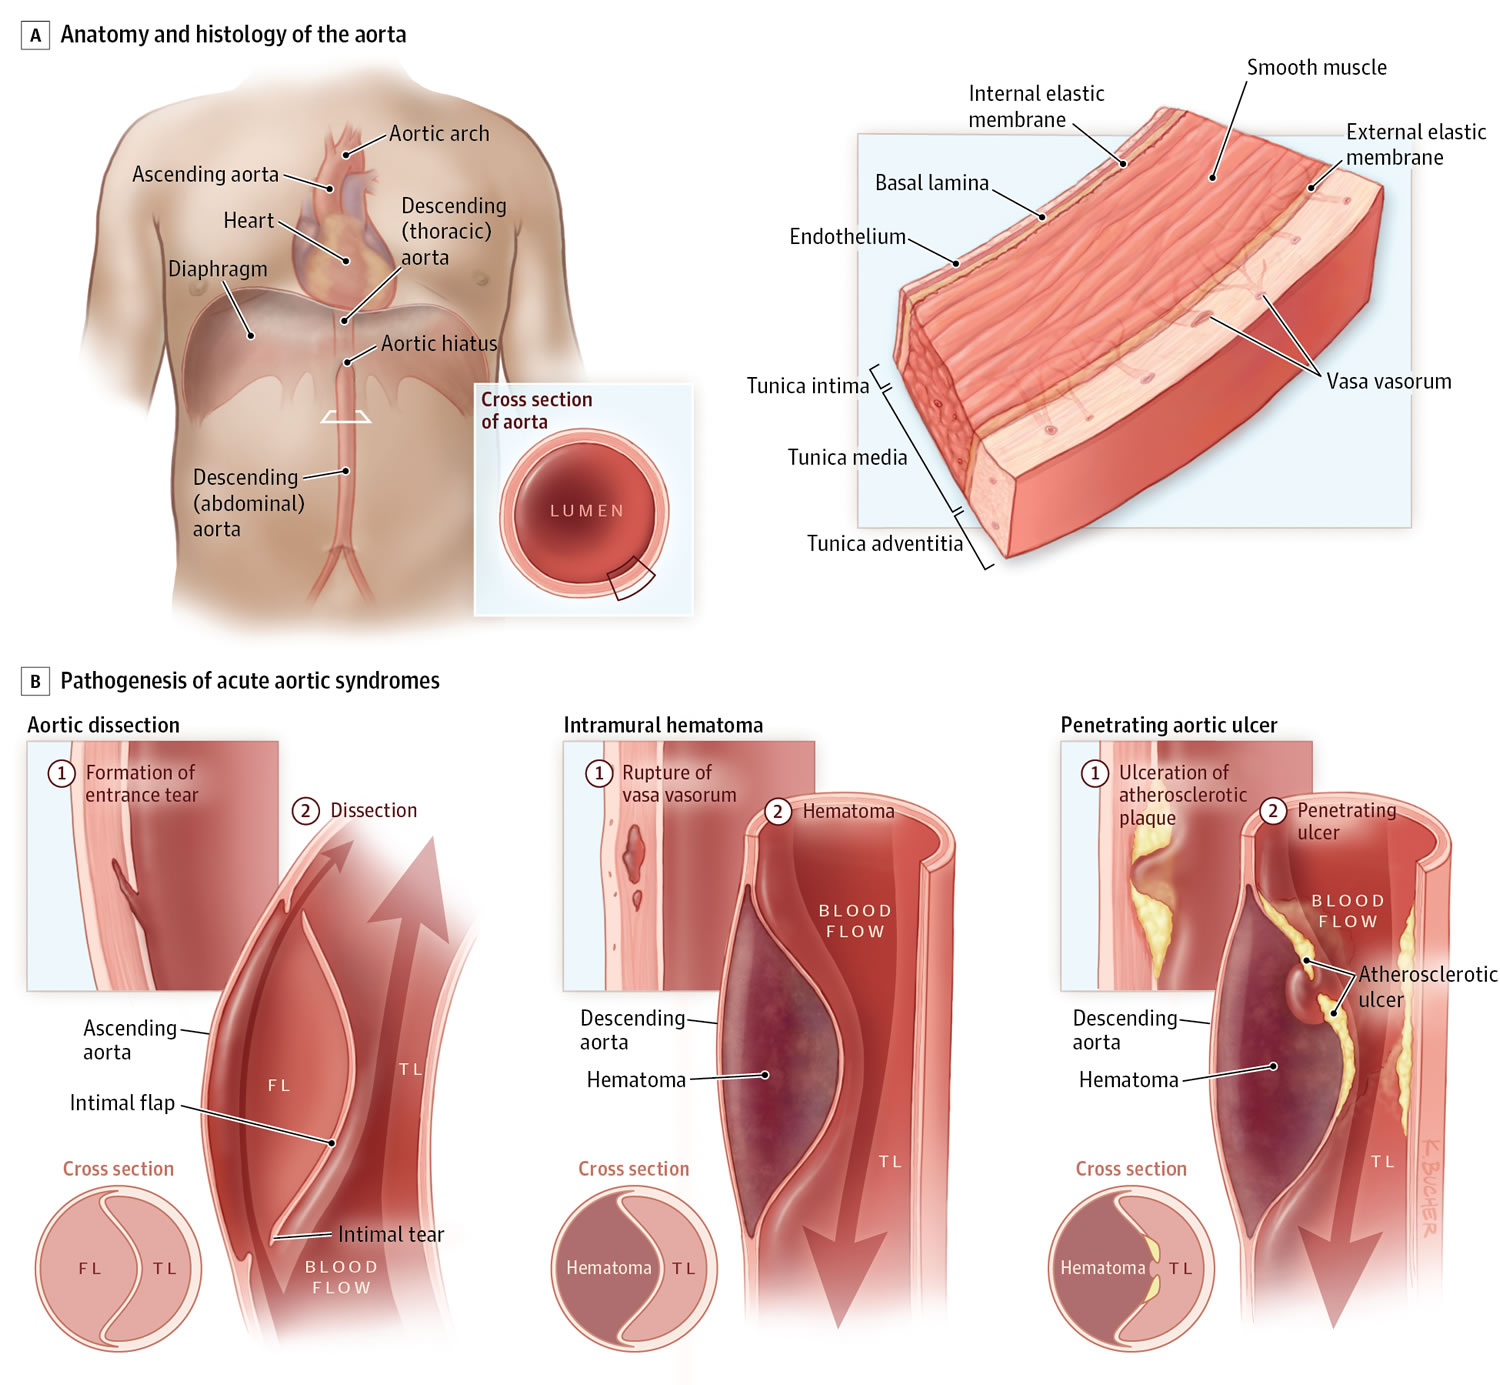

Aortic Dissection Without Chest Pain

Aortic Dissection Without Chest Pain

Aortic Dissection Chest Pain

Figure 4 CTA Showing A Type A Aortic Dissection Extending Along The

Thoracic Aortic Dissection CT Radiology At St Vincent s University

Computed Tomography With Contrast Enhancement In A Patient With Acute